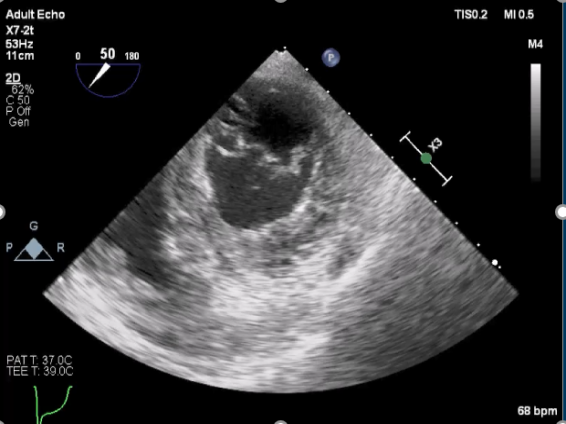

麻醉状态下TEE显示中大量返流MR:

房间隔穿刺:

Bicaval 寻找穿刺点

穿刺点距离二尖瓣环3.42cm